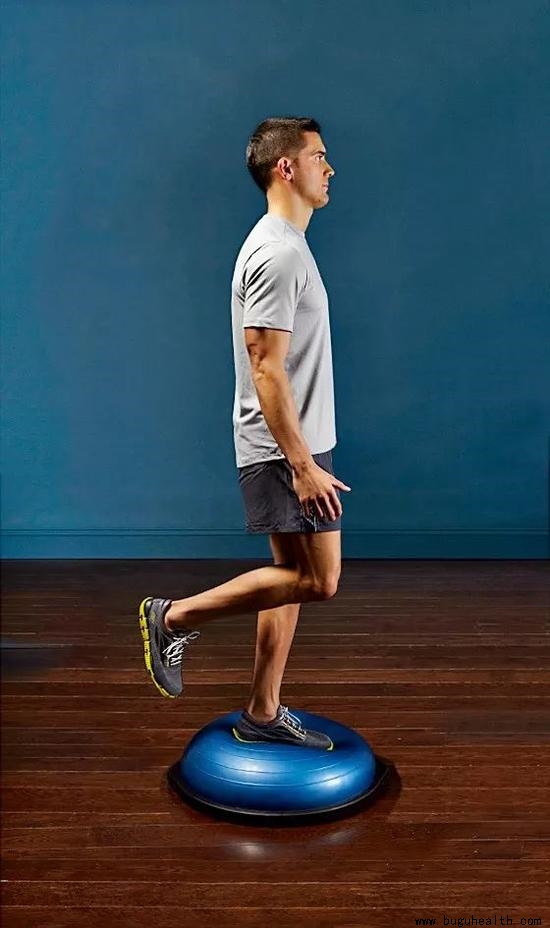

- 膝关节前交叉韧带损伤的发生率逐步增加,在膝关节韧带损伤中居首位。膝关节前交叉韧带损伤后导致膝关节不稳定可引起半月板损伤和退行性关节炎等继发损伤,严重影响患者日常生活和运动功能。目前,很多学者认为膝关节前交叉韧带损伤关节稳定性的重建,不仅包括生物力学的重建,而且应该有健全的神经肌肉反馈机制的重建。术后.....